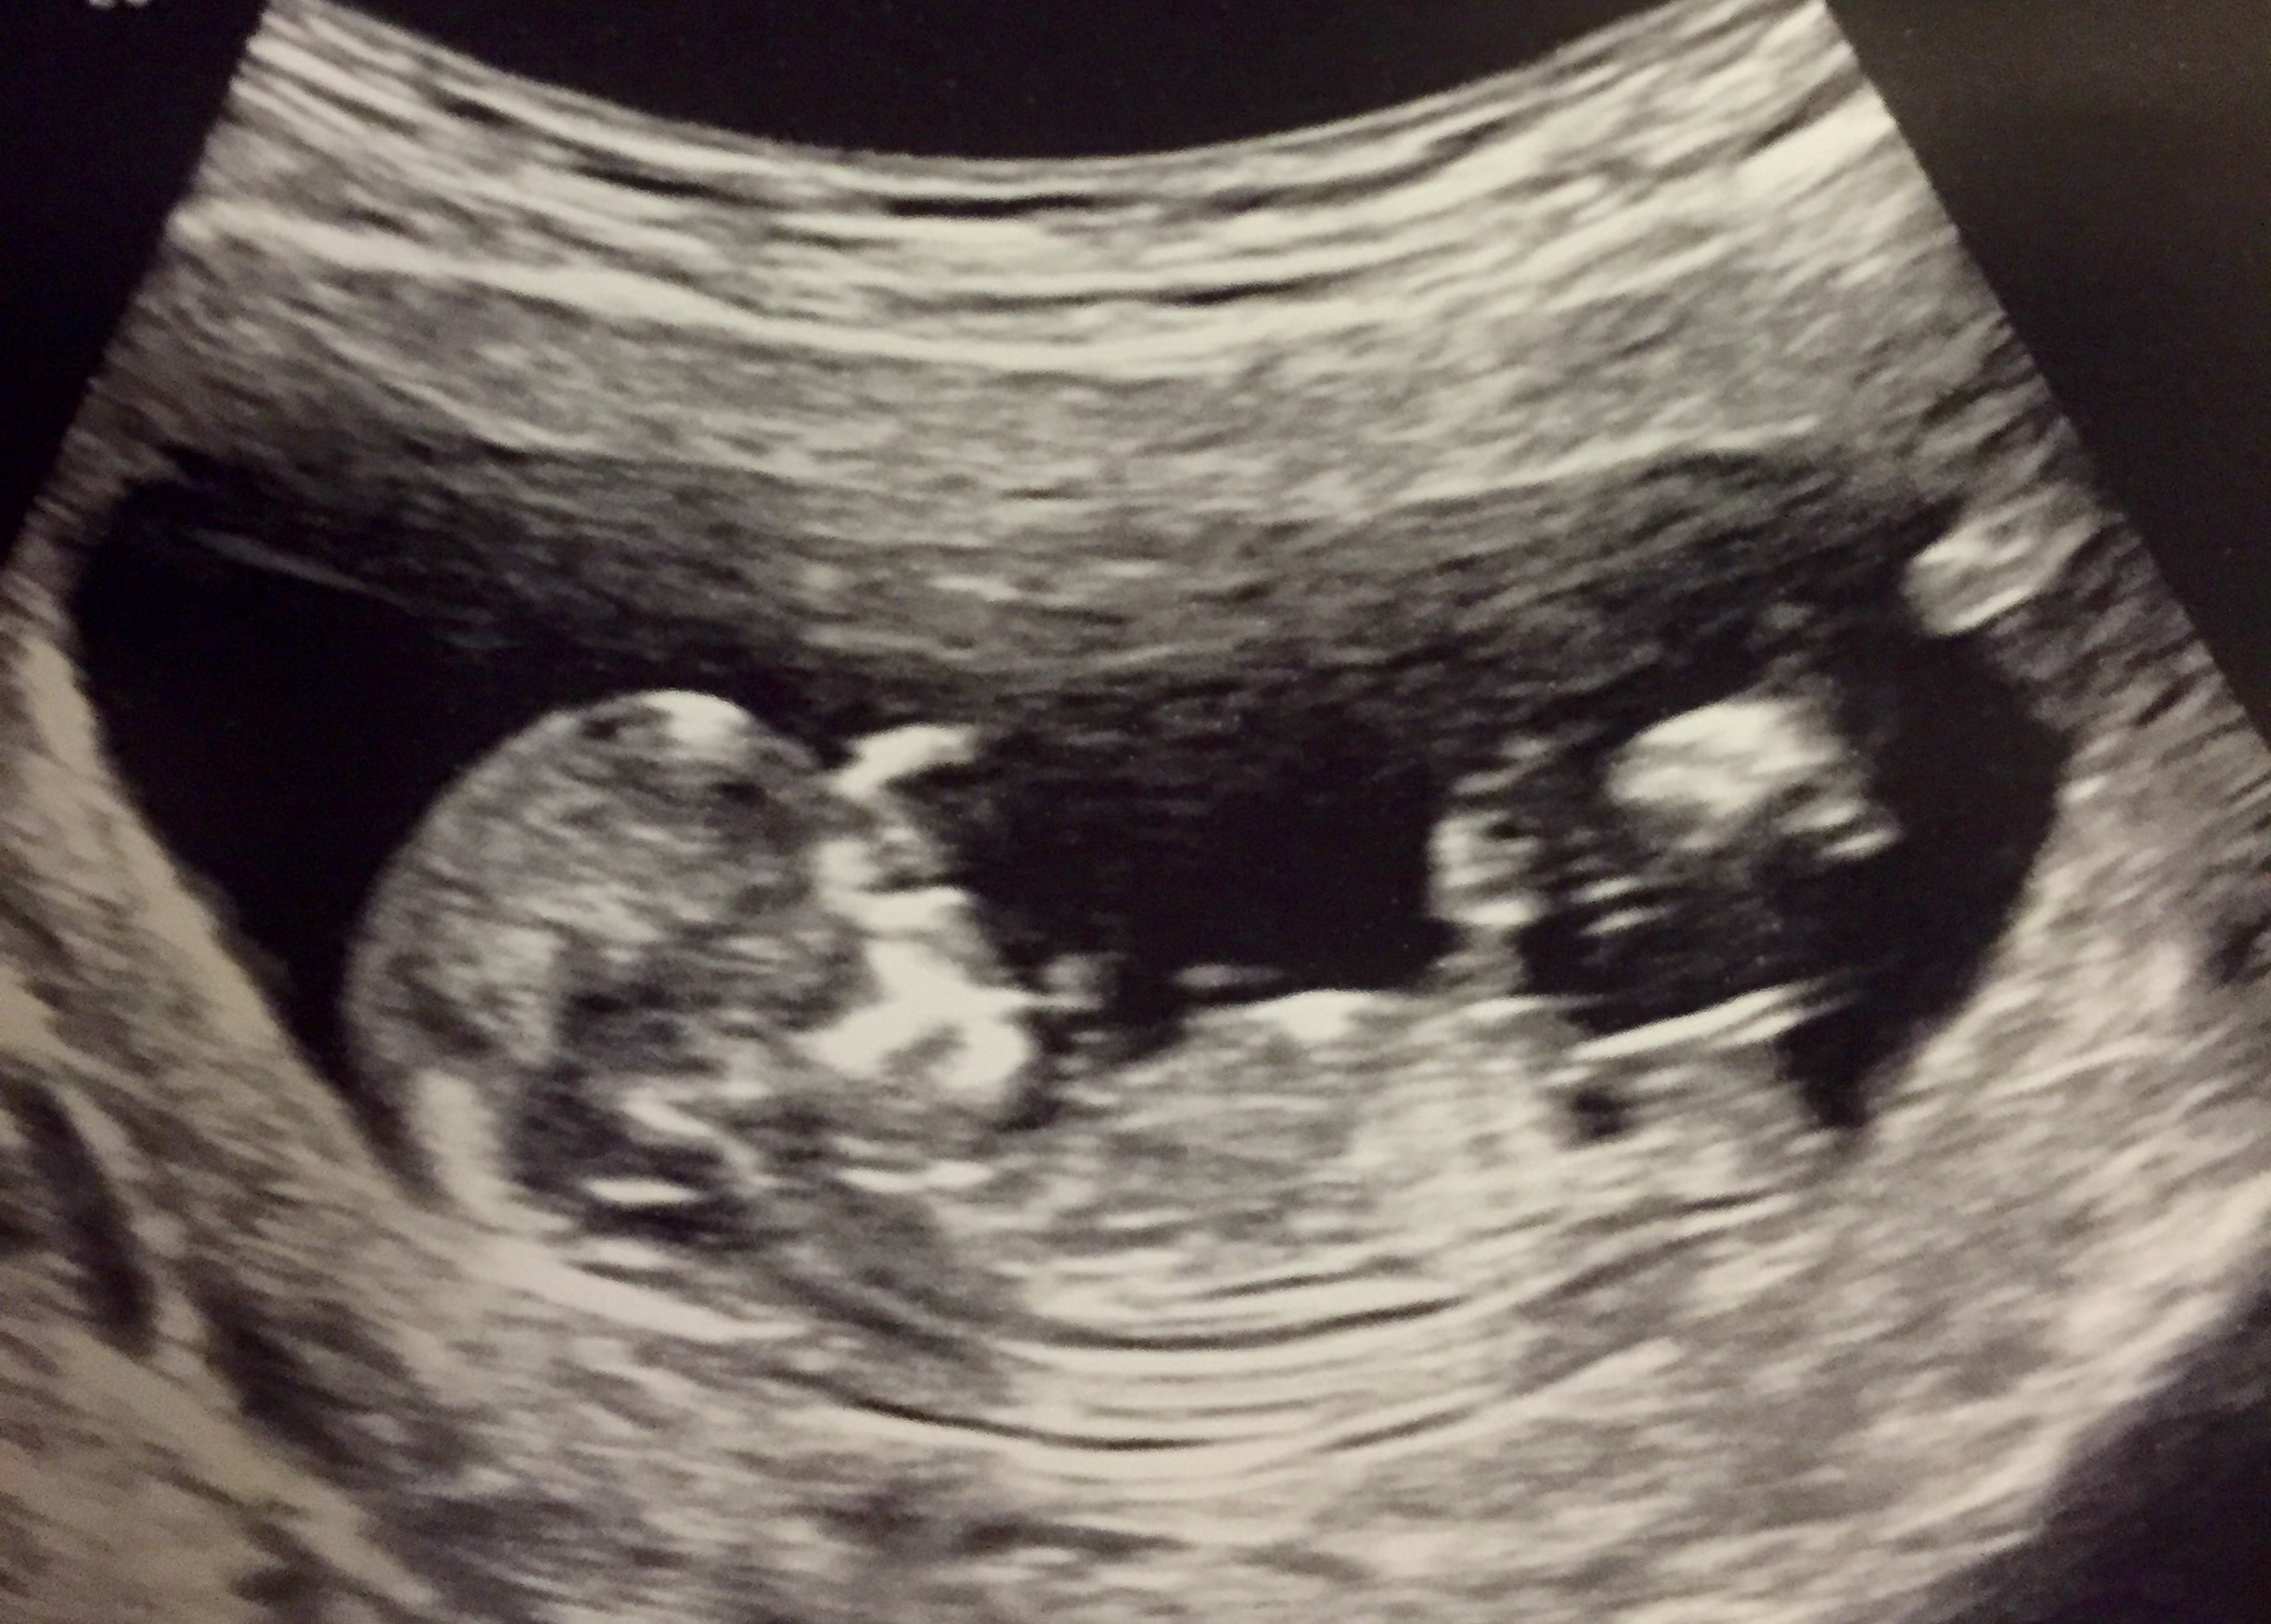

Thank you! Total newbie here. It hasn't felt real until this ultrasound. Our son died at 33 weeks, so this one won't really feel real until he or she is in our arms.

Re: Rainbow baby gender guess